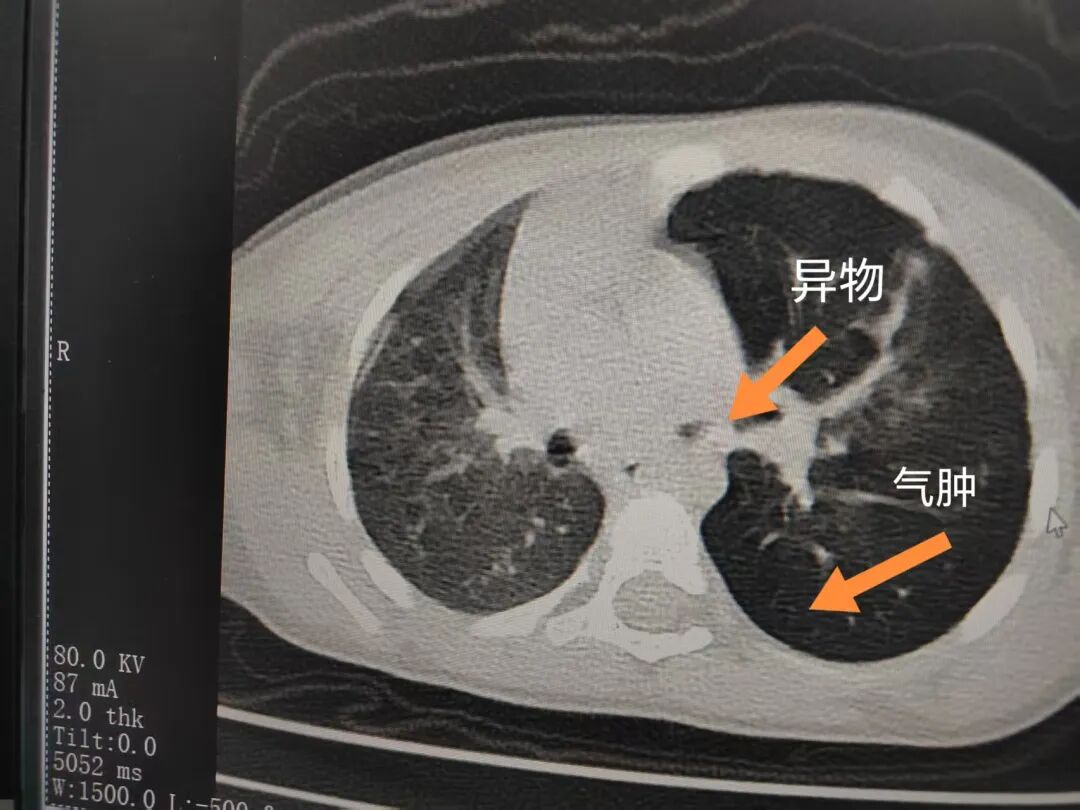

三天后(11月13日),趙寶出現(xiàn)高熱、咳喘加重,家長(zhǎng)著急了,再次帶他來(lái)到醫(yī)院。CT檢查顯示左肺過(guò)度充氣,左肺上下葉支氣管主干見不規(guī)則高密度影,左肺上葉可見大片狀密度增高影,縱隔窗實(shí)變,提示為“左側(cè)支氣管內(nèi)異物并繼發(fā)性改變,左肺上葉舌段肺膨脹不全”。

市二院小兒呼吸內(nèi)科團(tuán)隊(duì)迅速為患兒制定了周密的手術(shù)方案,并很快安排了氣管鏡探查。術(shù)中,主治醫(yī)師田慧等憑借嫻熟的氣管鏡操作技術(shù)成功將異物大塊板栗取出。由于板栗在氣管內(nèi)存留時(shí)間較長(zhǎng),質(zhì)地軟糯易碎,大大增加了手術(shù)難度。檢查還發(fā)現(xiàn),異物停留部位的氣管黏膜已出現(xiàn)充血紅腫、糜爛,導(dǎo)致患兒住院時(shí)間相應(yīng)延長(zhǎng)。此次事件給趙寶的家庭帶來(lái)了不小的驚嚇與擔(dān)憂,也再次為廣大家長(zhǎng)敲響了警鐘。

市二院小兒呼吸內(nèi)科副主任楊亞娟介紹,異物誤入氣道可能導(dǎo)致氣道阻塞,嚴(yán)重時(shí)可引發(fā)窒息,甚至危及生命。若異物進(jìn)入支氣管,造成不完全堵塞,可引起阻塞性肺氣腫;如完全堵塞支氣管,則可能導(dǎo)致肺組織萎縮,形成肺不張。此外,若異物存留時(shí)間較長(zhǎng),或?yàn)橹参镄援愇?,容易合并?xì)菌感染,產(chǎn)生膿性分泌物,進(jìn)而發(fā)展為肺炎。她強(qiáng)調(diào),盡早診斷并取出異物,是減少并發(fā)癥、降低病死率的關(guān)鍵。